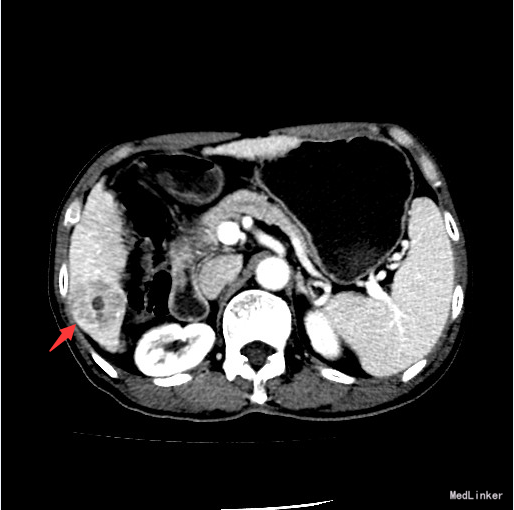

查体:腹部平坦,腹壁静脉无显露,腹壁柔,无压痛,无反跳痛。 辅查:腹部CT提示:肝S6段结节型肝癌。结节型肝硬化;门脉高压,食管胃底静脉、胃管状静脉、脾静脉曲张;脾稍大;少量腹水。

诊断:结节型肝癌 治疗:入院后完善相关检查,于全麻下行肝S6段肝癌切除术,术程顺利,术后予加强护肝、抗炎等治疗。

随访:(肝S6段肿物)形态结合免疫组化,符合高~中分化肝细胞性肝癌,未见确切脉管内癌栓形成;“切缘”未见癌;周围肝组织呈结节性肝硬化改变。 讨论: 结节型肝癌直癌结节直径小于5cm的肝细胞癌,影像表现呈“快进快出”表现。结节型肝癌的治疗仍以手术切除为首选,早期切除是提高生存率的关键,肿瘤越小,五年生存率越高。一般诊断明确,病变局限于一叶或半肝者,且肝功能代偿尚好,凝血酶时间不低于50%者,为手术切除适应症。若手术切除困难或者肝功能较差者,可以选择消融术或者肝动脉化疗栓塞术(TACE)等微创治疗。